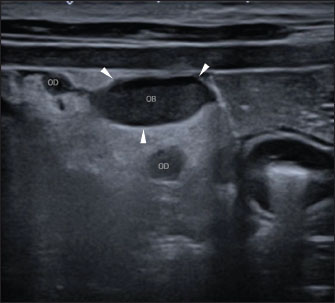

A Canon Aplio i600 ultrasound machine with convex (9-10.8 MHz) and linear (12-18 MHz) probes was used. The conscious patient was positioned in both the lateral and dorsal recumbencies. Moderate distension of both uterine horns (up to 17 mm in diameter) with immobile hyperechoic intraluminal content and irregular walls with multiple mural ovoid anechoic lesions were noted (Fig. 2). Cranial to the ovarian end of the right uterine horn and surrounding the right ovary, a 25-mm, well-defined, irregular lesion filled with mildly echogenic fluid was observed, which was compatible with a fluid-filled ovarian bursa. The adjacent peritoneum was moderately hyperechoic with a mild amount of free echogenic fluid (Fig. 3). A scant amount of free anechoic fluid was also present next to the uterine horns. A slightly tortuous tubular structure (up to 4 mm in diameter) with no color Doppler signal was identified running longitudinally adjacent to the ovary up to the uterine horn’s ovarian end, which was interpreted as the oviduct (Figs. 3 and 4). Moreover, both ovaries showed several rounded structures that were compatible with the corpora lutea. Vascularization near the lesion preserved the color Doppler signal.

Fig. 4. Abdominal ultrasonographic transversal examination in left lateral recumbency using a lineal high-frequency probe in B-mode. Lateral is to the left of the image. Note the right ovarian bursa (“OB”; the arrowheads mark the limits of the ovarian bursa), and parts of the thin, tortuous, tubular structure, compatible with the oviduct (“OD”; the highest one in the image is near the ovarian bursa, and the lowest one is next to the uterine horn’s ovarian end).